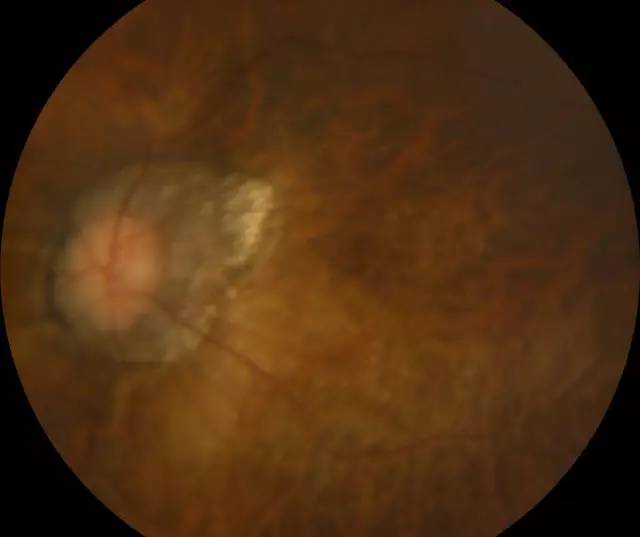

肖先生左眼术前眼底照相图

二天,赶上周末,家人陪着肖先生连忙赶到深圳太阳成tyc122cc(中国)集团进行诊治。经过一系列检查,确诊肖先生为超高度近视裂孔性视网膜脱离,由于黄斑区视网膜全部脱离,必须要尽快做手术。